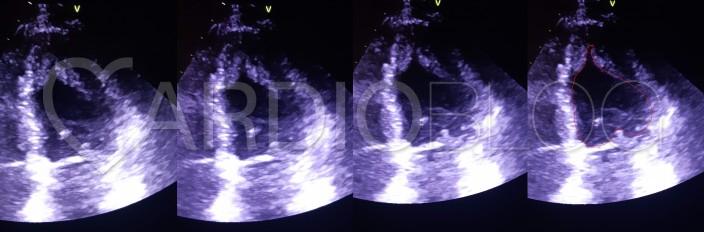

Aktuálisan ez látszott a technikailag nehezebben kivitelezhető echo-képeken (csúcsi nézet) systoléban:

Ha képalkotóval (szív-MR, echo, kamrai angiográfia) végül sikerül korrektül ábrázolni, akkor jellegzetes a bal kamra üregének pikk-szerű karaktere.

A szindróma jellegzetességeit összefoglaló (1976) leírójáról Yamaguchi-szindrómának nevezték el. Ez a hypertrophiás cardiomyopathia (HCM) egyik kevésbé gyakori, de jellegzetes alcsoportja. Az európai populációban ritka. Öröklődése a klasszikus HCM-hez hasonlóan autoszomális domináns, és ugyanazok a szarkomer gének érintettek, bár a mutációs spektrum részben eltérhet. A betegség gyakran fiatal felnőttkorban vagy középkorban manifesztálódik, és férfiakban gyakoribb. Az összes HCM-es beteg kb. 3–10%-át teszi ki, de bizonyos ázsiai (főként japán) populációkban jóval gyakoribb (akár a HCM-es esetek 25%-t is elérheti). Míg a klasszikus HCM inkább septalis dominanciájú és kiáramlási obstrukciót eredményezhet, e forma sajátossága, hogy a szívizom-megvastagodás túlnyomórészt a bal kamra csúcsára (apexére) lokalizálódik. Sokszor ebből adódik, hogy nehezebben fedezik fel, mert az olykor nehezen ábrátolódó csúcs elbújik az echocardiographia elől.